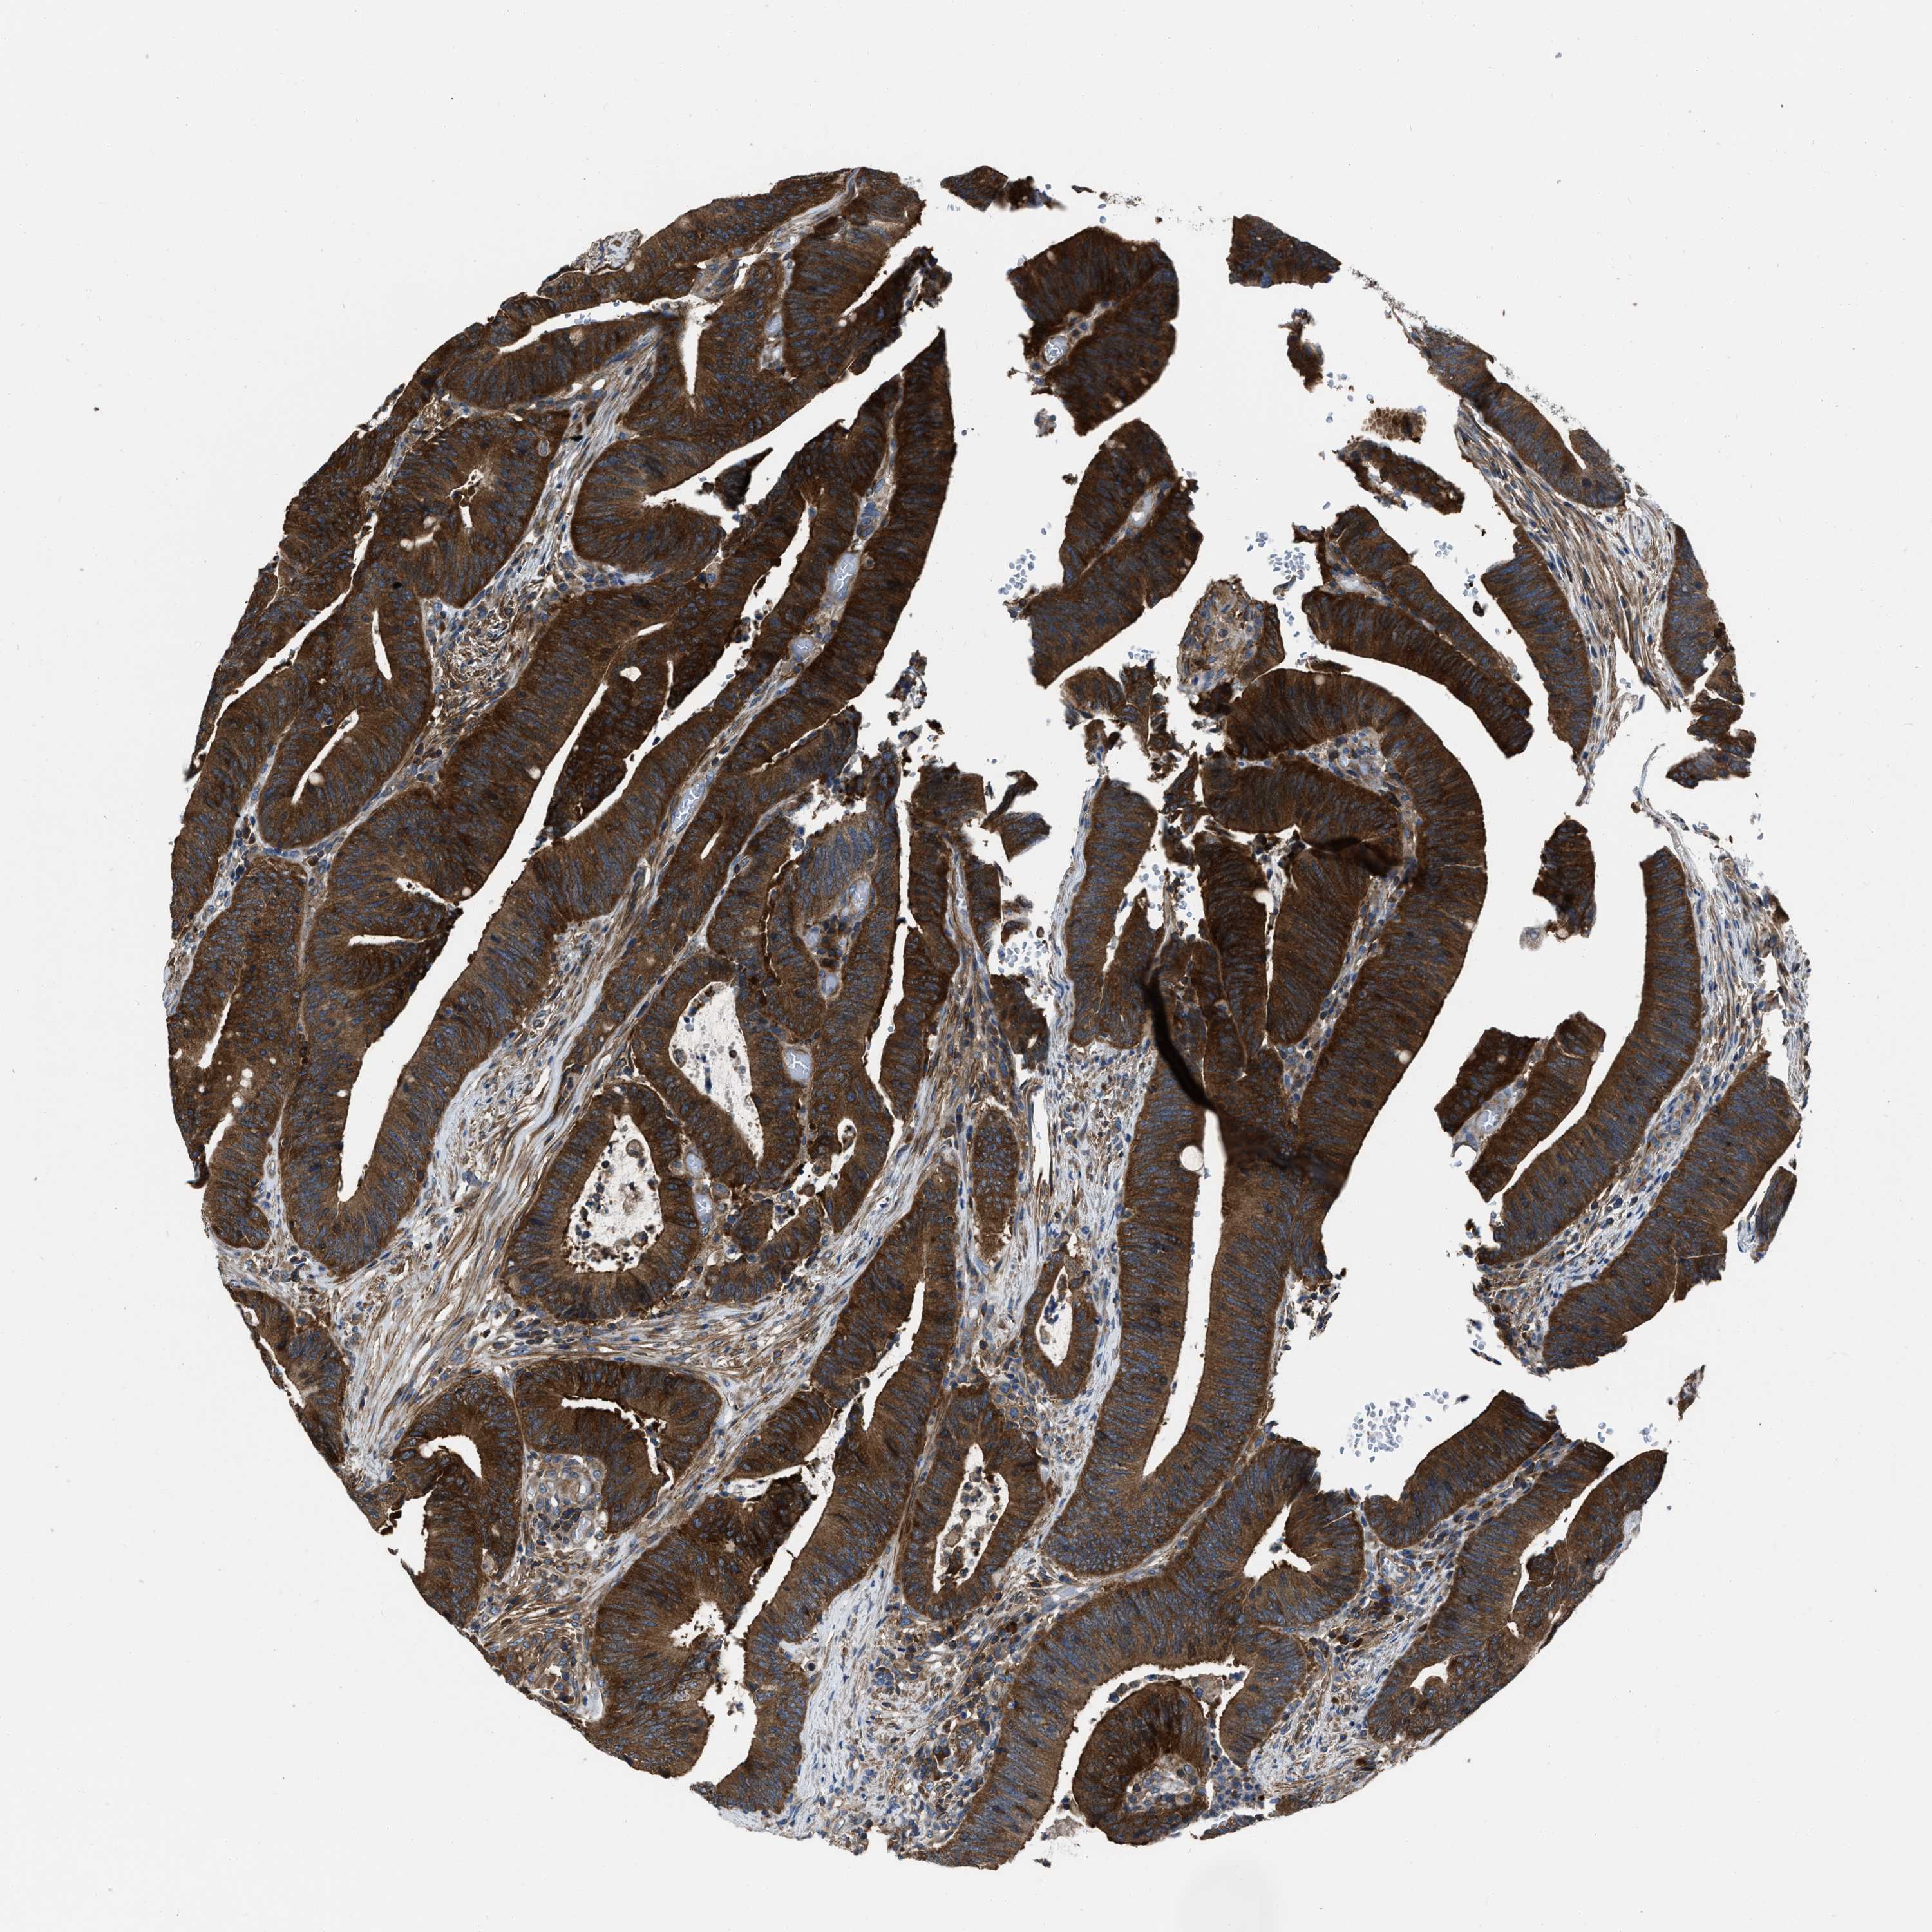

CANCER COLORECTAL CANCER Show tissue menu

Colorectal cancer

Human cancer

Colon adenocarcinoma

Rectum adenocarcinoma